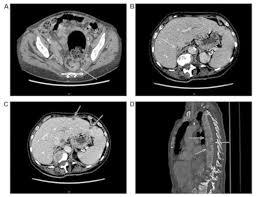

Find information metastatic cancer from the cleveland clinic, including symptoms & treatment options for when this happens, it is called metastatic cancer. What treatment options are available for metastatic colon cancer? Some colon cancer cells make markers that travel to the bloodstream. Therefore, a diagnosis from a physician is required to confirm or rule out a metastatic colon cancer diagnosis. Treatment options are important for someone with metastatic colon cancer. The liver is one of the places it can go. Nearly all types of cancer have the ability to metastasize, but whether they do depends on a variety of individual factors. Metastatic colon cancer can be diagnosed with the use of blood tests and other diagnostic examinations. Bowel cancer is the third leading cause of cancer in the u.s. Metastatic cancer may develop several years after the primary cancer is first diagnosed and treated. Ct and mri are the modalities most frequently used for staging. Get the facts on colon cancer (colorectal cancer) signs, symptoms, causes, prognosis, treatment what exams and tests diagnose colon cancer? Dysplasia is a precancerous condition which means that there is an area in the polyp that contains cells that look abnormal.